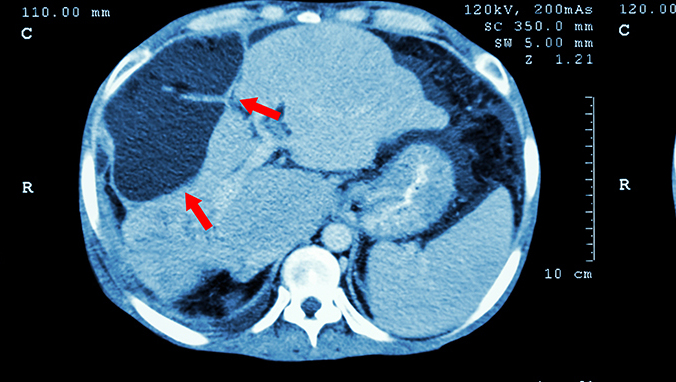

胰头癌主要症状时因压迫或阻塞胆道而引起的无痛性、逐渐增加的黄疸,因缺少胆汁入肠,患者大便呈白陶土样。胰体尾部癌临床上常无黄疸,发病更为印尼,常因癌组织侵入门静脉而产生腹水,压迫脾静脉发横脾肿大,侵入腹腔神经丛而发生深部疼痛。同时还可有消瘦、贫血、呕吐、便秘等症状。

胰头癌早期可直接蔓延到邻近组织,如胆管及十二指肠,随后即经淋巴道转移至胰头部及总胆管旁淋巴结。但肝内转移最为常见,尤其以体尾部癌更为多见。癌组织还可侵入腹腔神经丛周围淋巴见习,发生远隔部位的淋巴道或血道转移。

胰腺癌可发额很难过与胰腺的头、体、尾部或累及整个胰腺,但以胰头部最多,约占到六到七成,发生于胰体者次之,尾部最少见。肉眼观肿瘤成圆形或卵圆形,比娜姐有的分明,有点弥漫浸润于邻近胰腺组织难以分辨,镜下主要有腺癌,未分化癌,鳞状细胞癌这三种类型。